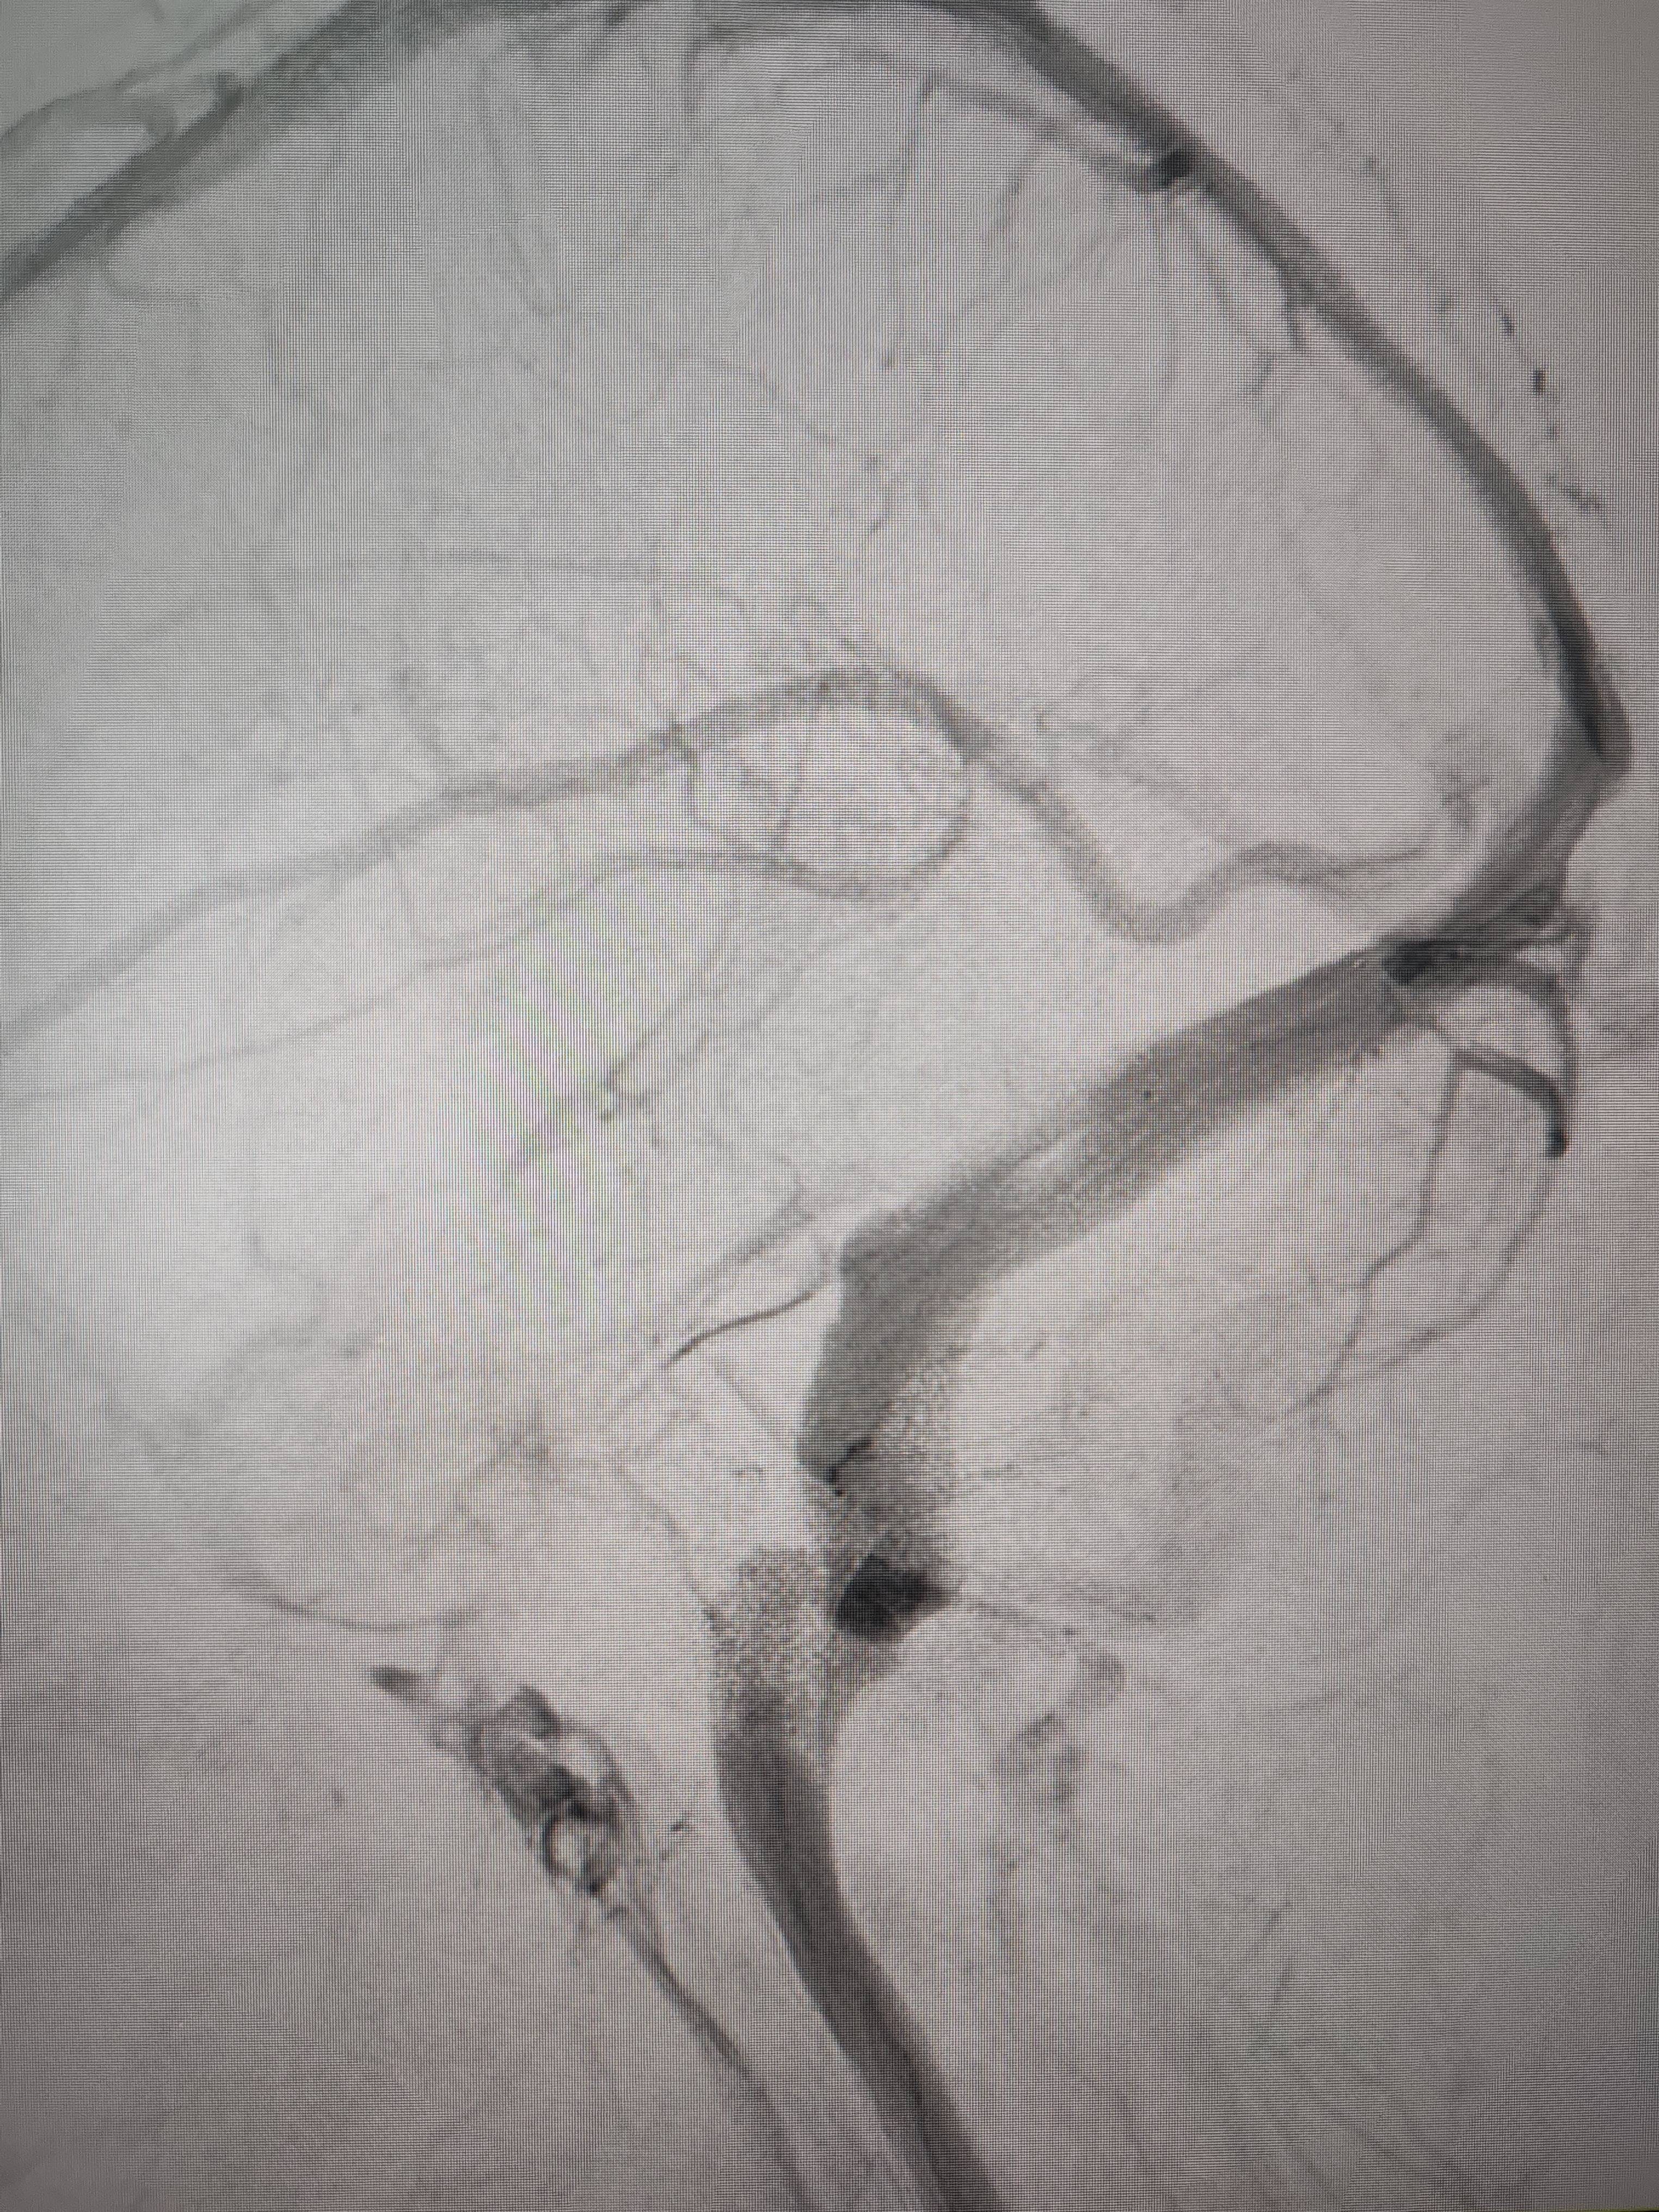

患者造影图像显示,其耳侧静脉窦狭窄。 南方+ 欧阳少伟 拍摄

李宝民举例说,通过查体、CT、造影等影像技术的检查,患者赵女士是由于静脉窦狭窄,导致缓慢的静脉血流也出现“湍流”现象,其拐弯、打漩涡、回流产生的声响,又顺着骨传导,传至耳蜗处,进而让患者出现搏动性耳鸣的症状。

经过静脉窦支架置入手术治疗后,患者的静脉窦“堵点”被打通。 南方+ 欧阳少伟 拍摄